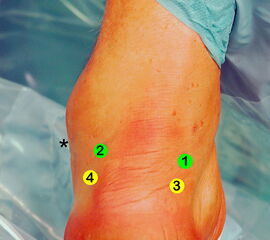

Abbildung 3

Übersicht der Arthroskopiezugänge für den arthroskopischen FHL-Transfer.

1 = posteromediales Portal.

2 = posterolaterales Portal.

3 und 4 = tiefe paraachilläre Portale.

Die hohen paraachillären Zugänge befinden sich auf Höhe der Außenknöchelspitze (*) unmittelbar medial und lateral der Achillessehne. Um den N. suralis nicht zu verletzen, wird die Haut nur vorsichtig inzidiert und die Weichteile werden mit einem Klemmchen aufgespreizt.

Gelegentlich kann intraoperativ die Anlage tiefer paraachillärer Zugänge erforderlich sein, um den Tuber calcanei adäquat darstellen zu können (siehe auch Kapitel „Endoskopische Therapie der Haglunddeformität“, Abbildungen 2-4).

Zum Lesen der Bildbeschreibung und zur Vollansicht bitte das Bild anklicken. Foto: M. Galla.